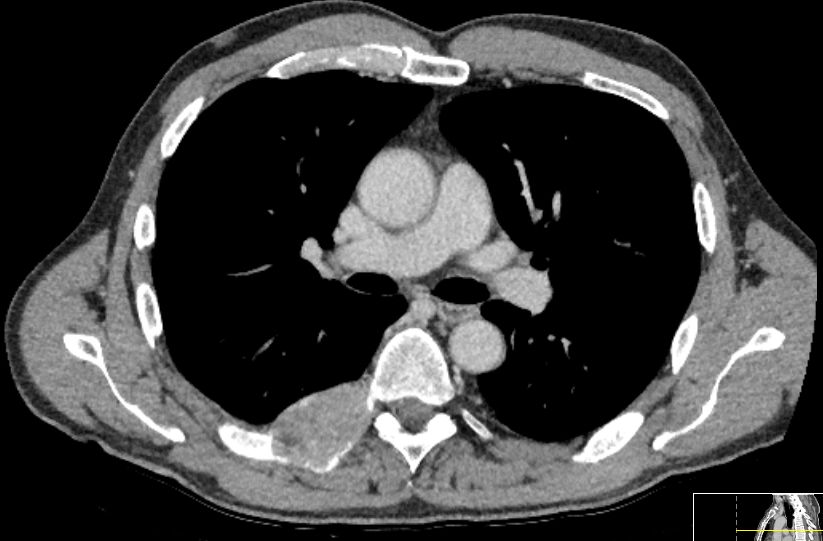

8 Jahre später: Nach zahlreichen Operationen,

interstitieller Brachytherapie z.Z. intraabdominaler Tumor beherrscht. Jetzt

Metastase am Ansatz der 7. Rippe rechts mit drohendem Einbruch in den

Spinalkanal.![]() |